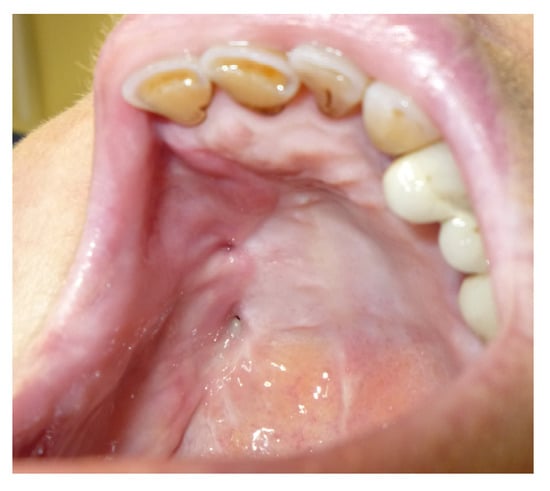

3.1.3. Case 3: R.M.

| R.M. | X | * | 9 | 0 | ||